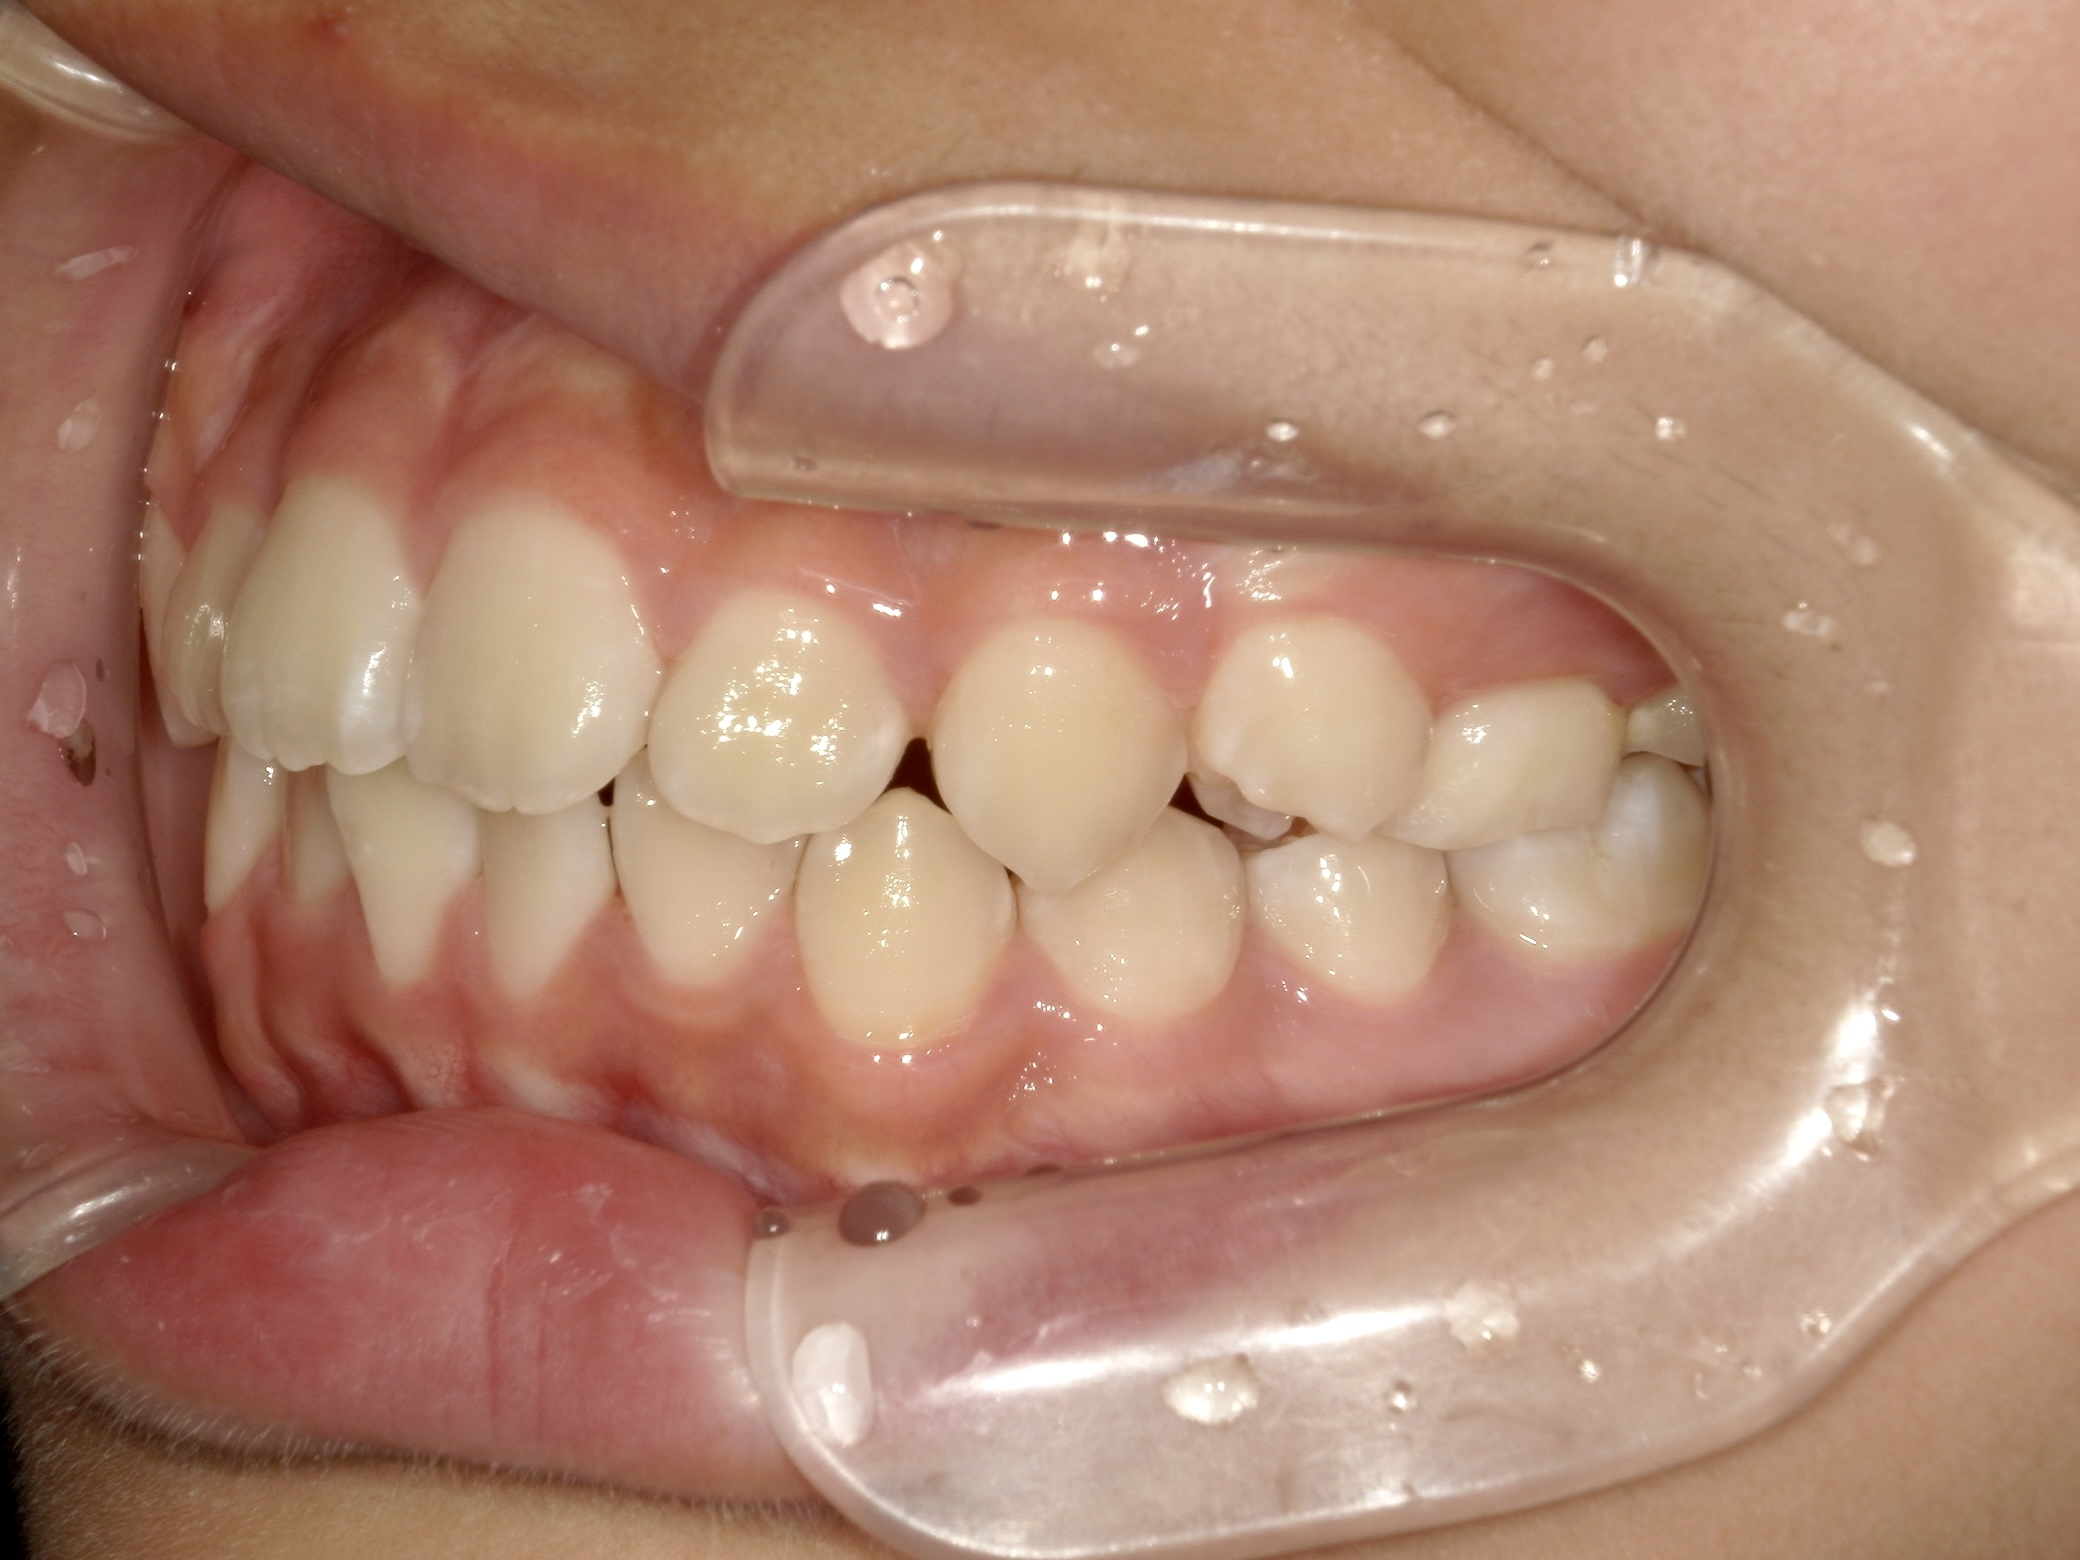

治療中/横から見た歯並び

出っ歯傾向がなくなり、噛み合わせも改善しているのがわかります。 現在永久歯への生え変わりを待っている期間です。 今後は再評価後に一期治療で終了するか、二期治療へ移行します。 -